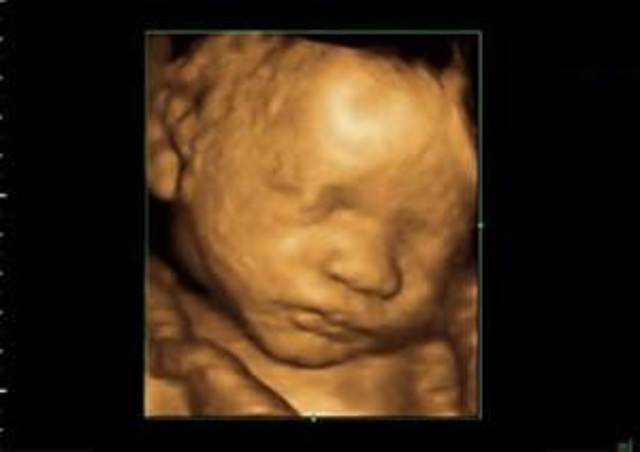

During week twenty-two the eyebrows, eyelids and fingernails of the baby are fully developed. Being aware of sounds around it, a loud noise can wake the baby inside the womb.

• Week 23

Week 23

By week twenty-three the baby can turn side to side inside the womb; also skin pigment starts to form in the baby.